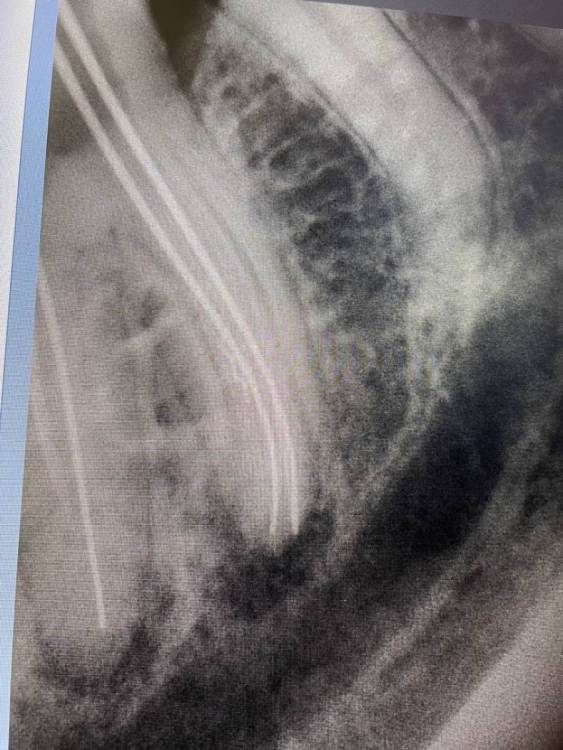

1586Doc Опубликовано 8 декабря, 2021 Автор Поделиться Опубликовано 8 декабря, 2021 Добавим эндо) Ретрит 46 зуб, 2 фрактуры в медиальных каналах. Один достаем, второй обходим )) 1 3 Ссылка на комментарий

1586Doc Опубликовано 25 декабря, 2021 Автор Поделиться Опубликовано 25 декабря, 2021 (изменено) ну и пломбировка 46 зуб, далее 6-12 месяцев ожидания. Изменено 25 декабря, 2021 пользователем 1586Doc 1 2 Ссылка на комментарий